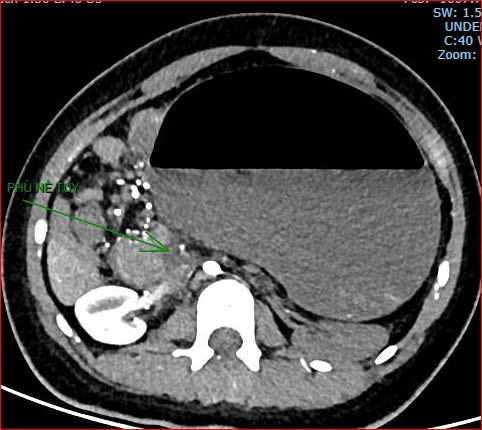

Khoảng 21 giờ 40, kết quả chụp CT cho thấy bệnh nhân rơi vào tình trạng cực kỳ nặng và hiếm gặp, bao gồm: xoắn dạ dày, nhồi máu thận trái, nhồi máu lách, viêm đầu tụy, viêm hỗng tràng, kèm dịch ổ bụng và tràn dịch màng phổi, trên nền bệnh nhân mắc hội chứng Down và tim bẩm sinh.

Hình ảnh chụp CT ổ bụng cho thấy dạ dày giãn lớn, xoắn bất thường; kèm tổn thương nhồi máu lách và viêm tụy trên nền ca bệnh hiếm, diễn biến đặc biệt nặng - Ảnh Bệnh viện cung cấp